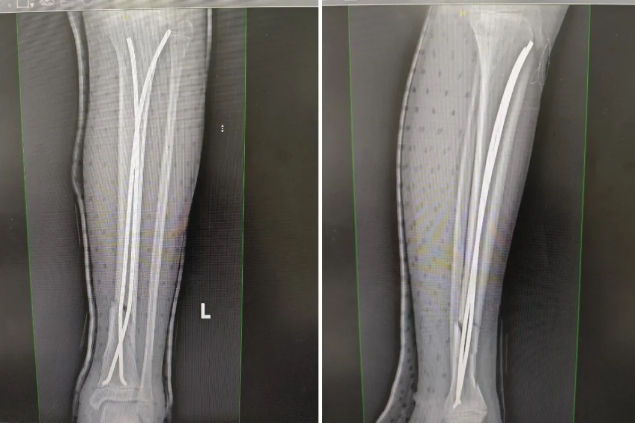

在完善相关术前检查后,祝振华主任带领小儿外科手术团队为小辉实施手术。术中,祝振华主任凭借丰富的临床经验和精湛的技术,在C臂机透视下精准复位骨折断端,并巧妙地通过两处1cm的纵行切口,先后置入两枚直径为3.5mm的弹力髓内针进行固定。整个手术过程出血量不到20ml。术中透视显示骨折断端复位满意,内固定在位有效,长短适宜。同时,为了最大程度减少术后疤痕对外观的影响,祝振华主任还为小辉进行了美容缝合。历时50分钟,手术顺利完成。

▲骨折断端复位满意,内固定在位